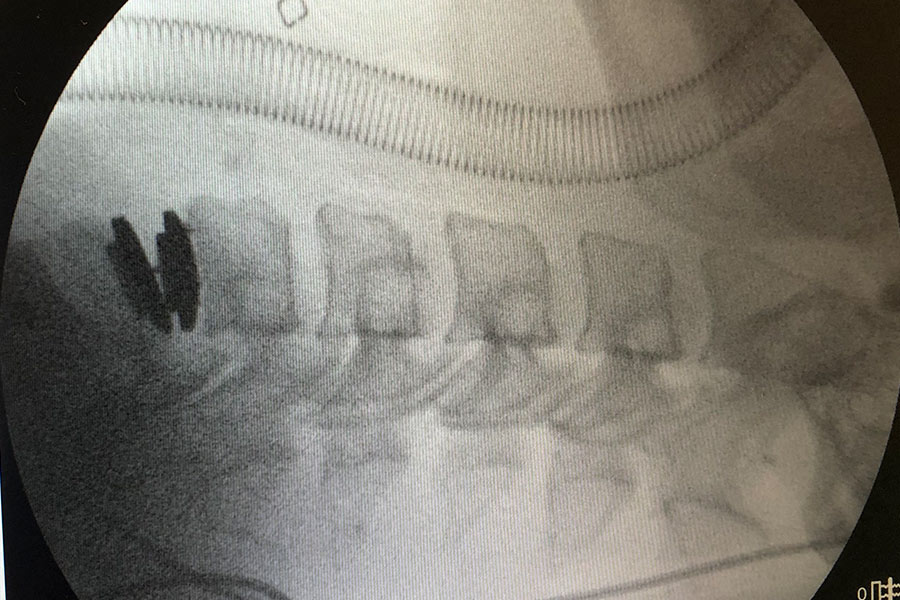

El paciente es un poco complejo, operado previamente con otro equipo de doctores. Le realizan una cirugía entre la 6º y la 7º vértebra cervical, con un intento de artrodesis.

Esta cirugía resulta finalmente insuficiente para la dolencia, ya que no han conseguido la fusión buscada con dicho tratamiento.

Como consecuencia de este fallo de funcionamiento, el paciente entra en fase de pseudo artrosis, lo cual le causa gran cantidad de dolor al haber una ligera movilidad en dicha pieza.

Se retira el implante intersomático y, tras una limpieza completa del ‘terreno’ tanto la parte intercervical como el canal, se implanta una prótesis cervical móvil.

cirugia-protesis-cervical-compleja